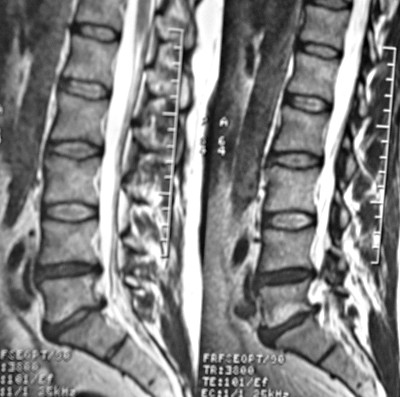

Riduzione degli spazi intersomatici

Questa condizione viene indicata al riguardo della colonna vertebrale.![]() |

![]() |

Indicano l'avvicinamento di due corpi vertebrali per degenerazione del disco vertebrale, che diventa più sottile.

Conflitti recidivanti di inadeguatezza a sopportare il carico, sentirsi schiacciati.